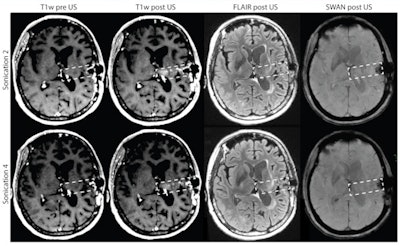

Contrast-enhanced MR images revealed that no BBB disruption was achieved in patients receiving treatments at acoustic pressures of 0.5 or 0.65 MPa. Overall, BBB disruption was observed in 28 of the 41 sonications -- eight of 11 sonications at 0.8 MPa, six of seven sonications at 0.95 MPa, and all 14 sonications at 1.1 MPa -- without detectable adverse effects.

The trial is still ongoing, as the maximum tolerated ultrasound dose has not been reached. However, data to date are sufficient to infer that transient BBB disruption with the SonoCloud system can be achieved with a threshold pressure dose of 0.8 MPa. Preliminary findings indicate the approach is safe and well tolerated in patients with recurrent glioblastoma and has the potential to optimize chemotherapy delivery in the brain.

The researchers note that, although the trial's primary objective was not to assess treatment efficacy, in nine patients with confirmed BBB disruption, the region encompassed by the ultrasound field had no detected tumor progression on MRI. If efficacy holds up in further trials, the technique may offer a new treatment strategy for patients with brain cancer and potentially also neurodegenerative disorders.